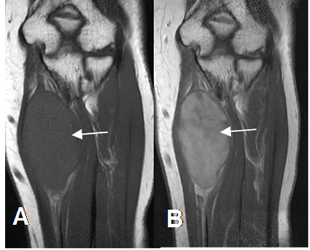

A: RM coronal en T1 simple y B: RM coronal en T1 con contraste. Imagen fusiforme que sigue la topografía del nervio ulnar, con realce del contraste secundario a neurofibroma.

Fig 176. Neurofibroma.